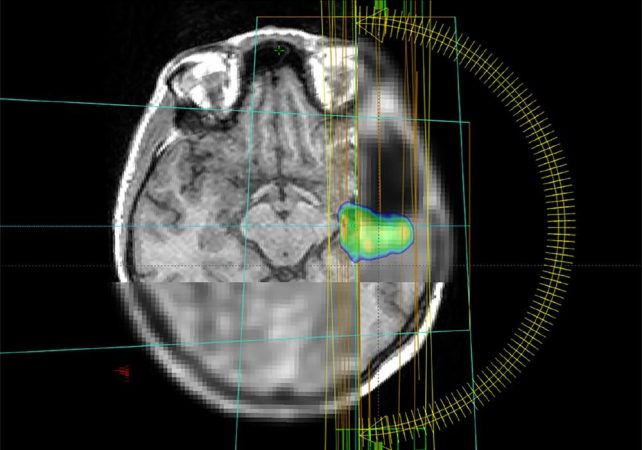

Statt wie bisher meist nur Bilder aus dem Magnet-Resonanz-Tomografen (MRT) zu verwenden, nutzt das Forschungsteam aus Spanien, Deutschland und Österreich in der aktuellen Studie auch auf die Positronen-Emissions-Tomografie (PET)-Bildgebung. „Wie wollen durch die Kombination aus MRT und PET die biologischen Eigenschaften der Tumore besser verstehen. Damit wird der Stoffwechsel im Tumor sichtbar und eine hochwirksame Bestrahlung besonders gefährlicher Tumoranteile möglich“, sagt die Physikerin Monserrat Carles Fariña, die sowohl in Valencia, Spanien, als auch am Universitätsklinikum Freiburg im Projekt aktiv involviert ist.

Ein weiterer Fokus der Studie liegt auf dem Einsatz von Künstlicher Intelligenz: Sie hilft, den Tumor auf den Bildern genauer zu definieren und vorherzusagen, wann und wo er möglicherweise wieder auftreten könnte. Ein großes Ziel der Forscher*innen ist die Schaffung eines frei zugänglichen digitalen Tools. Dieses soll es Krankenhäusern weltweit ermöglichen, die Therapie des Glioblastoms auf das individuelle Risikomuster von einzelnen Patient*innen abzustimmen und so die Lebensqualität der Betroffenen zu erhöhen. Das Projekt bringt Spezialist*innen aus den Bereichen Künstliche Intelligenz, Radioonkologie, Nuklearmedizin, Neuroradiologie, Medizinphysik, Neuropathologie und Neurochirurgie zusammen.